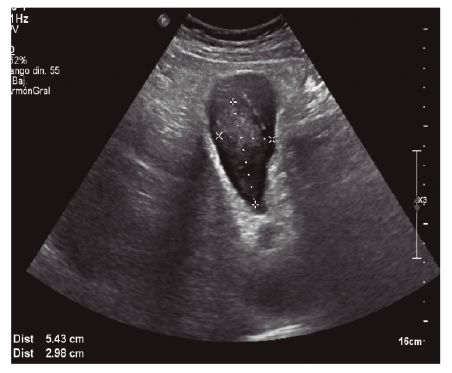

Presentamos el caso de un paciente que sufre un traumatismo abdominal cerrado por coz de caballo observándose en pruebas de imagen engrosamiento de la pared de la vesícula biliar con contenido hemorrágico como único hallazgo, sin otras lesiones asociadas intraabdominales.

Paciente de 38 años sin antecedentes personales de interés que acude a Urgencias por traumatismo abdominal cerrado por coz de caballo. A su llegada a nuestro Centro se encuentra estable hemodinamicamente. A la exploración destaca dolor a la palpación en hipocondrio derecho sin signos de irritación peritoneal. Se solicita analítica en la que destaca cifra de hemoglobina de 11,9 g/dL y transaminasas levemente elevadas, no constaban analíticas previas. Ante la estabilidad del paciente se solicita ecografía (Figuras 1 y 2) que se completa con TAC (Figura 3).